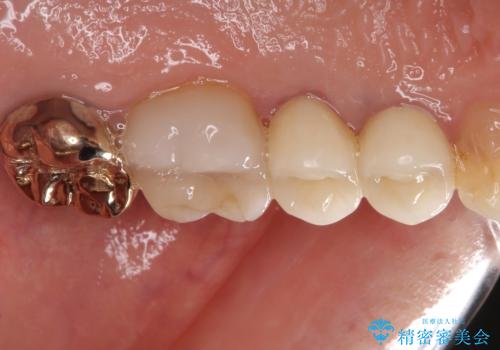

古くなったメタルボンドをオールセラミッククラウンに

- 歯肉が退縮したためにクラウンの縁や歯根が見えてしまっていることを気にして来院された患者様です。

また、歯肉が黒く変色していることも気になるとのことでした。

仮歯に変える際に歯肉の一部を切除し、金属片による変色を除去した後、オールセラミッククラウンにて補綴することとしました。